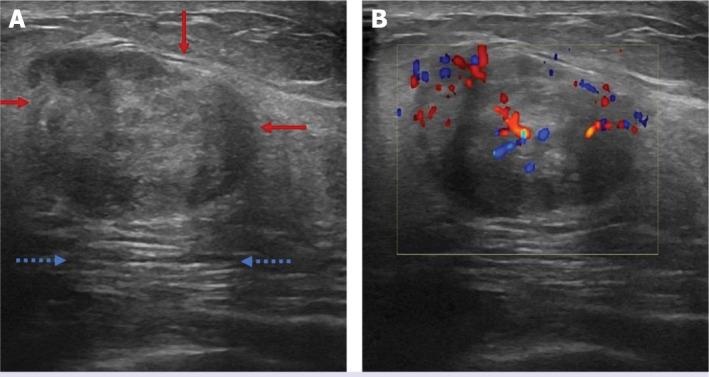

Myofibrolastoma of the breast (MFB) is a rare and benign stromal tumor. Although MFB is a benign entity, in radiologic evaluation, there is no specific diagnostic feature. Conventional breast imaging findings have been published before. Sonoelastography has been used as an imaging method that allows us to evaluate tissue stiffness in vivo and increases the specificity of B-mode ultrasonography in the discrimination of benign-malignant lesions. In this case report, it was shown that MFB is of high stiffness in shear wave elastography (SWE) evaluation. SWE findings of MFB, which is a benign lesion, have been described for the first time in the literature.

乳腺肌纤维母细胞瘤(MFB)是一种罕见的良性间质肿瘤。尽管MFB是良性病变,但在放射学评估中,没有特异性的诊断特征。常规乳腺影像学表现此前已有报道。超声弹性成像作为一种成像方法,能让我们在体内评估组织硬度,并提高B型超声在鉴别良恶性病变方面的特异性。在本病例报告中,显示出MFB在剪切波弹性成像(SWE)评估中具有高硬度。MFB作为一种良性病变的SWE表现,在文献中首次得到描述。